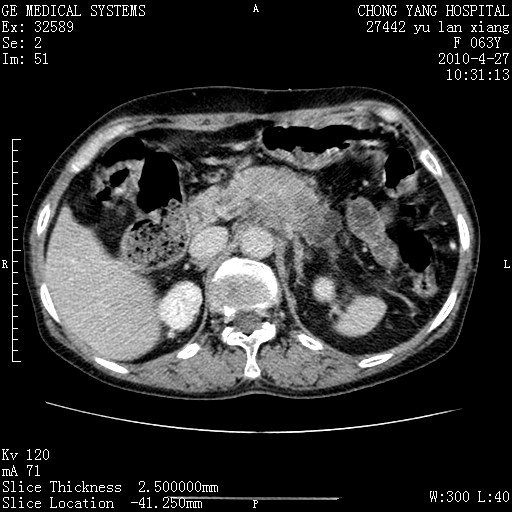

标题: CT26066:F63Y 上腹正中压痛半月,CA199:7400u/ml,MR示胰腺炎伴 [打印本页]

胰腺癌侵犯腹腔动脉干-分支、胃壁、左侧膈肌伴胰周及腹膜后淋巴结转移、胆囊切除术后。

胰腺癌侵犯腹腔动脉干-分支、胃壁、左侧膈肌伴胰周及腹膜后淋巴结转移、胆囊未显影。